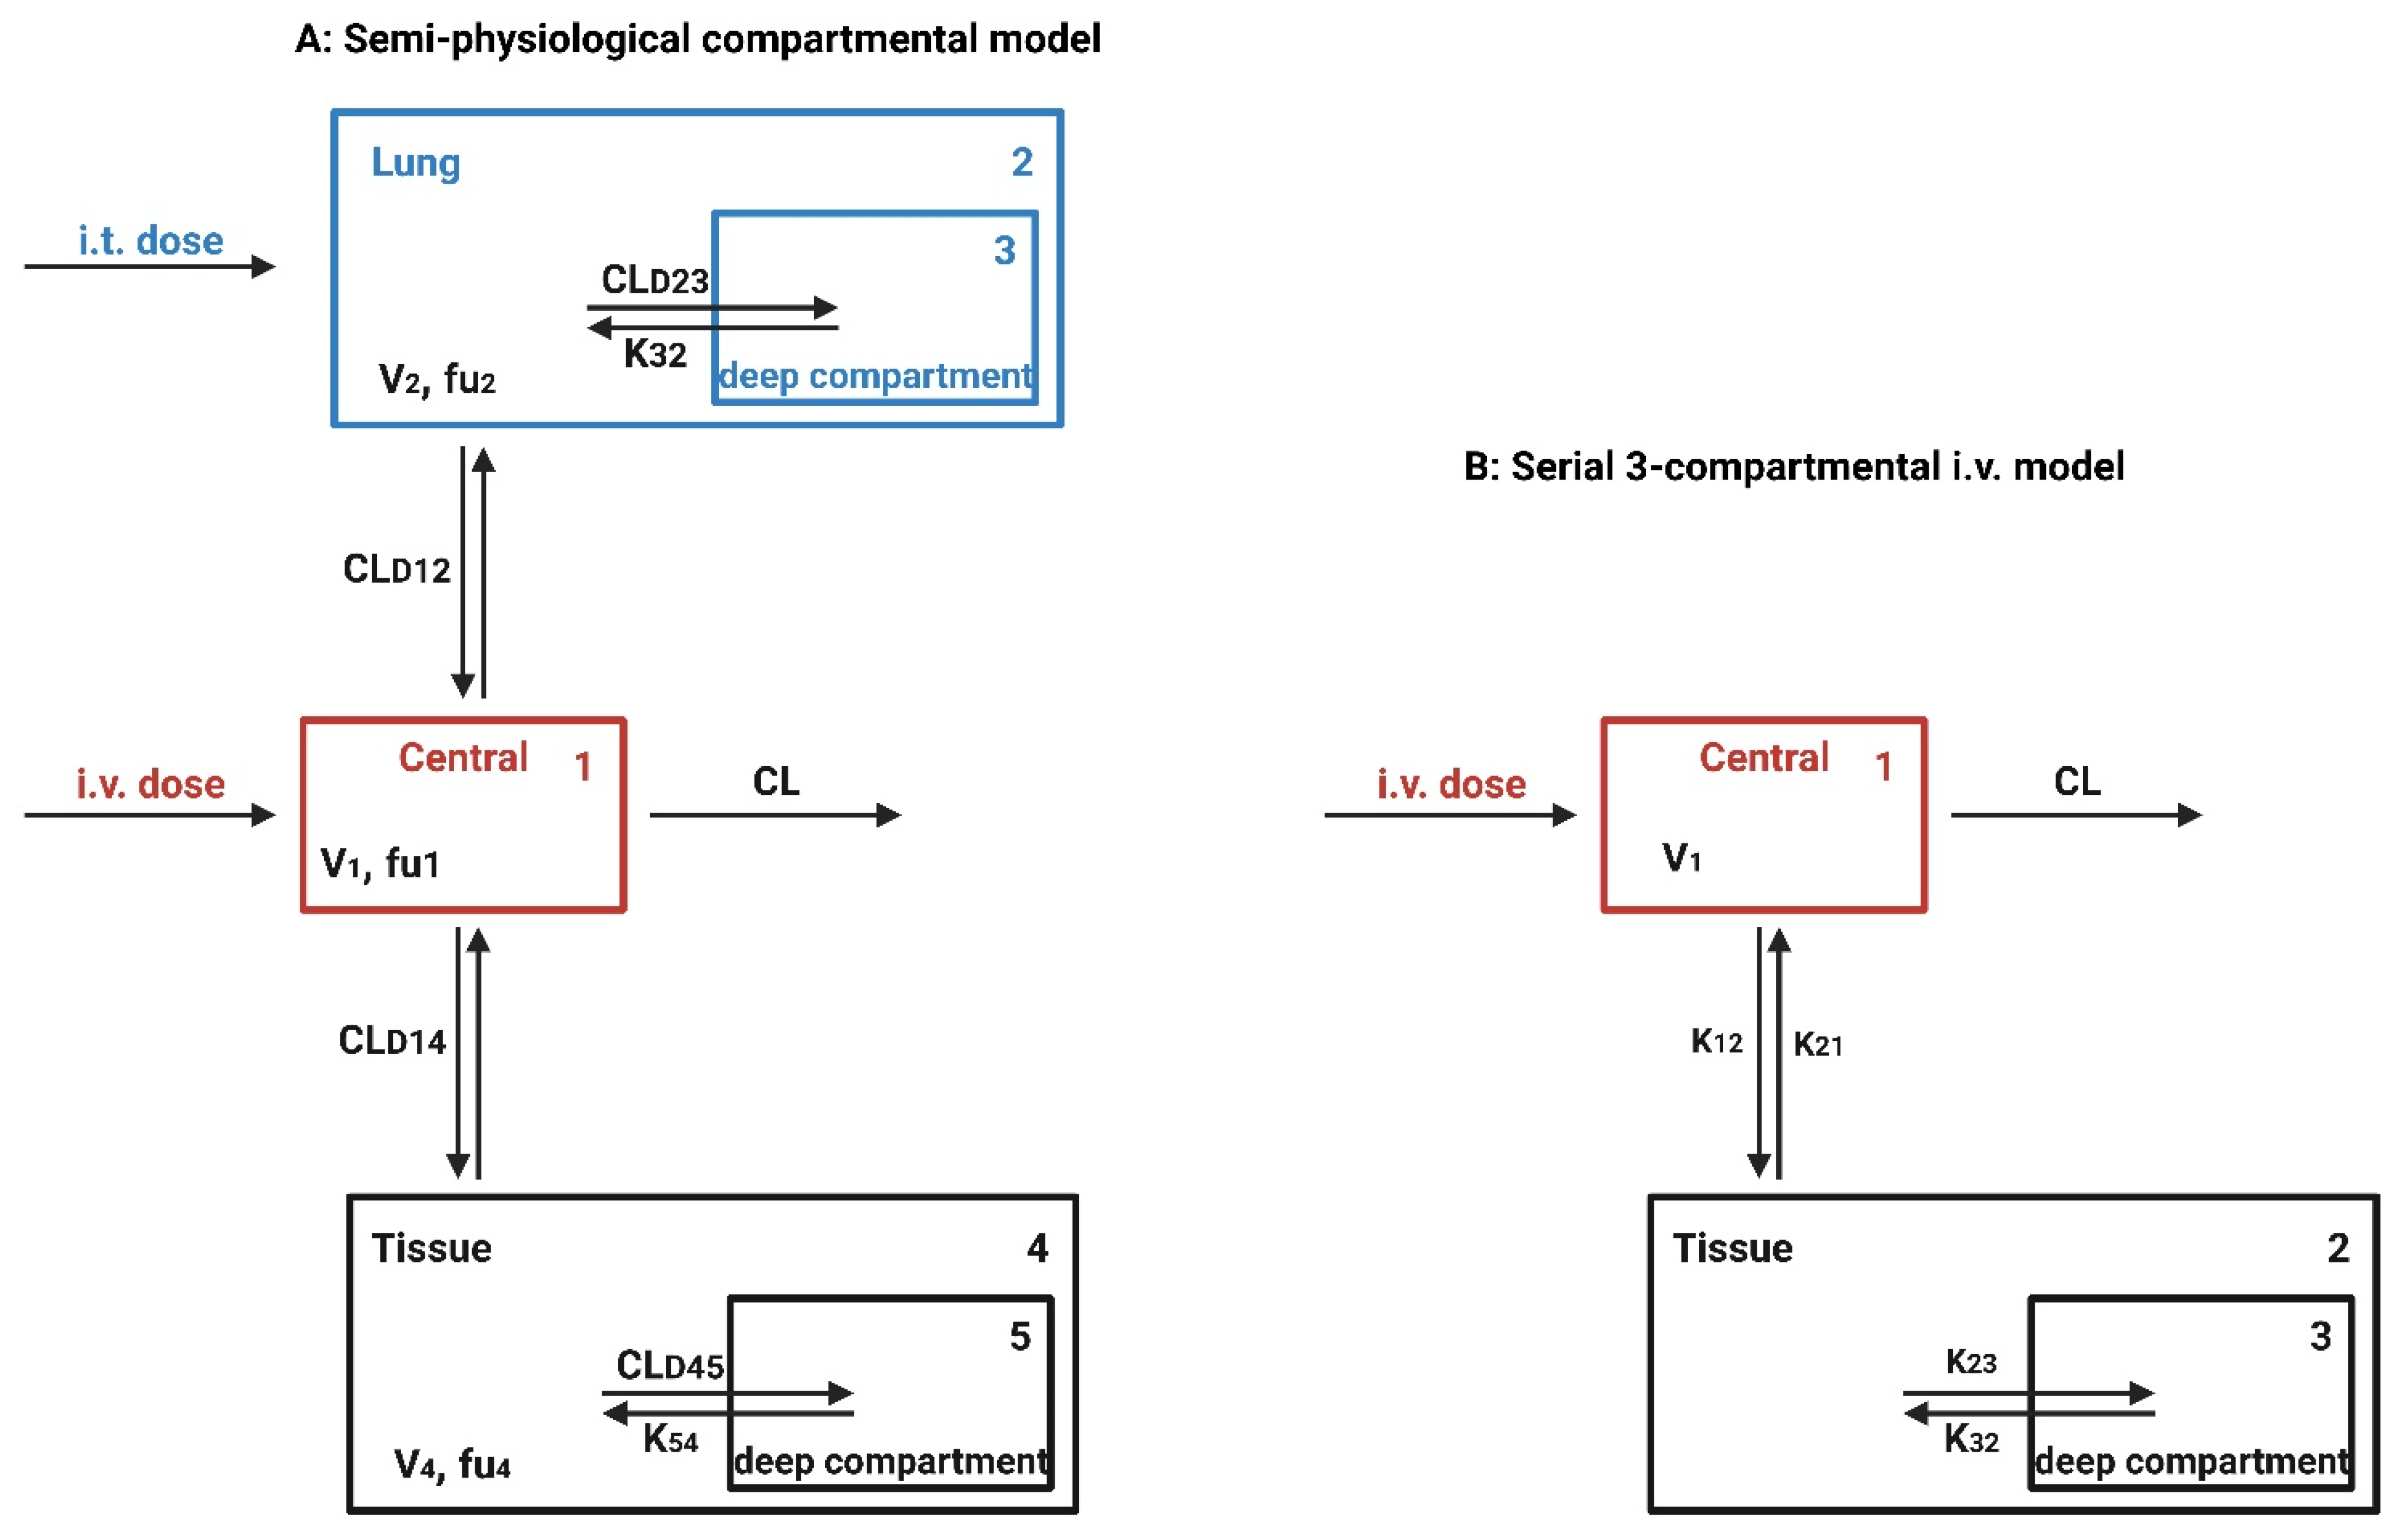

8.1. Pharmacological/PKPD Challenges